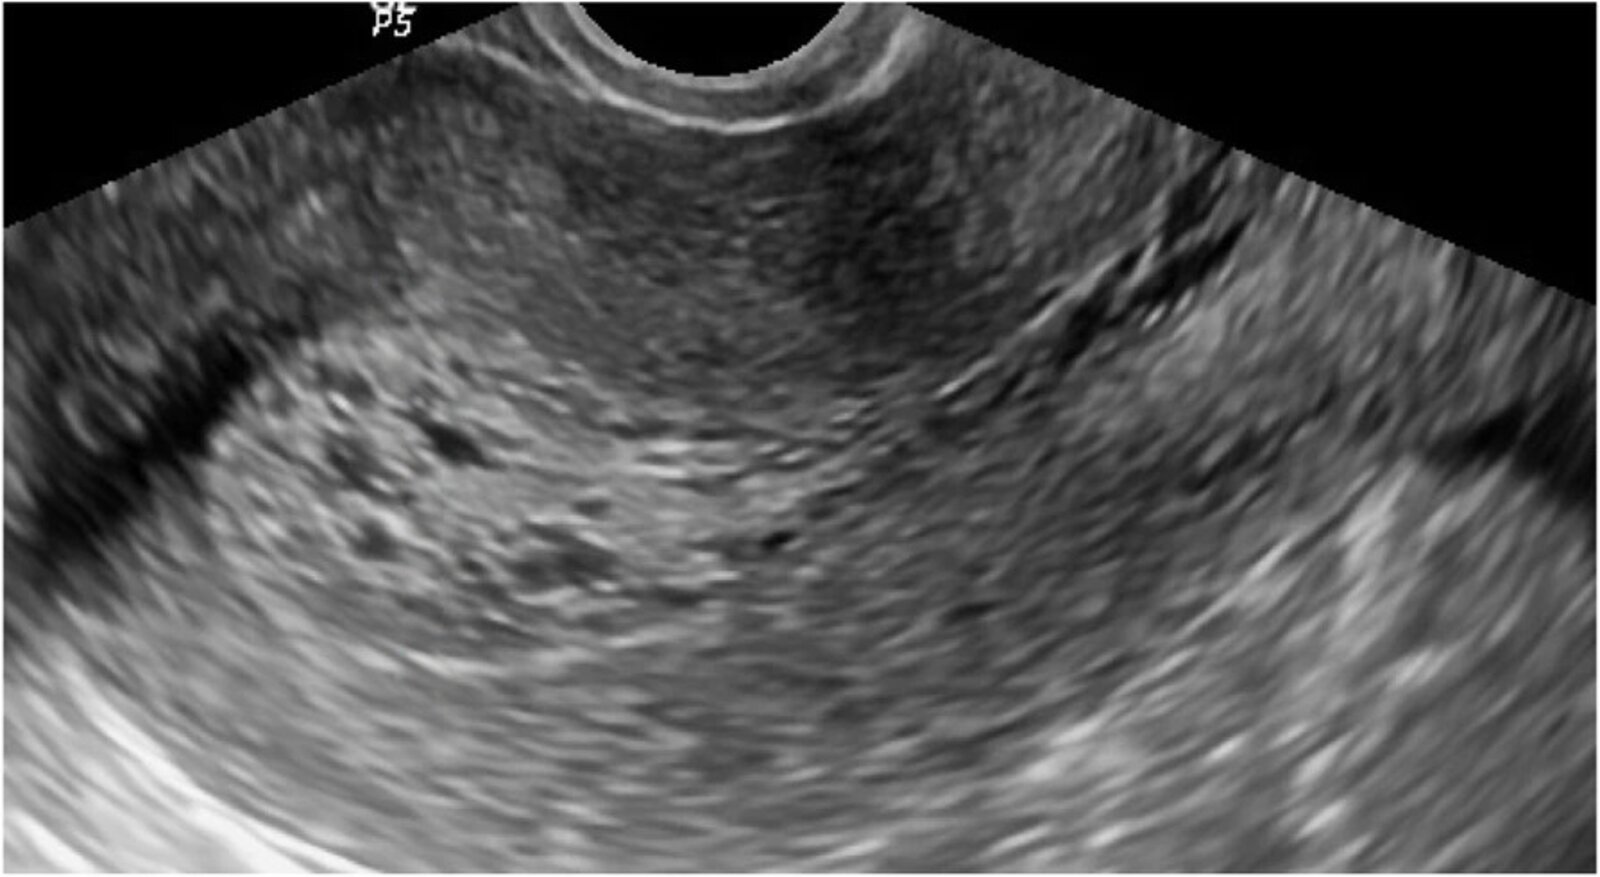

• TVUS with color Doppler ultrasound ; [7][23]

• First-line imaging for suspected endometrial polyp(s)

• Findings include: [19][24]

• Focal, homogeneous, echogenic endometrial mass with preserved endometrial-myometrial interface

• Distortion of the usual endometrial contour (interrupted mucosa sign)

• A single blood vessel supplying a polyp may be visible with color Doppler ultrasound [7]